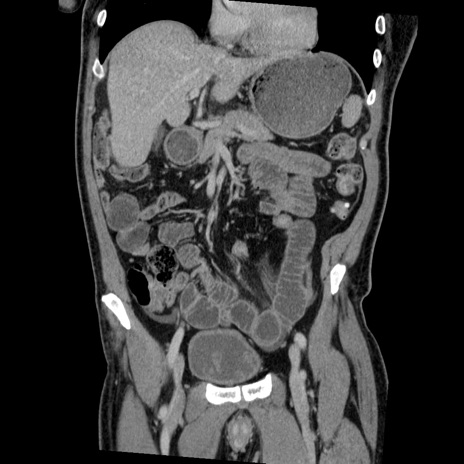

症例22(冠状断像)

【症例】50歳代男性

【主訴】腹痛

【現病歴】AVMからの被殻出血のため回復期リハ病棟入院中。 本日午後3時頃急に下腹部痛が出現した。

【既往歴】AVM、被殻出血、虫垂炎、高血圧

【身体所見】意識晴明、左半身不全麻痺、会話の理解は良好、36.5°C、腹部:膨隆、全体に板状硬、下腹部正中に圧痛点あり、反跳痛-、筋性防御不明、右下腹部にope scar

【データ】WBC 9400、CRP 0.06